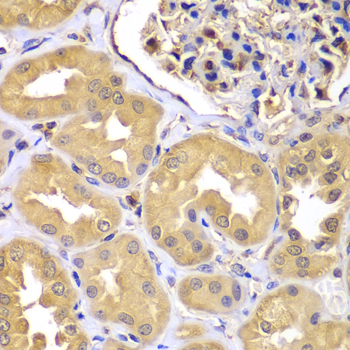

• A7350: image 2

Immunohistochemistry of paraffin-embedded human kidney using LZTR1 antibody at dilution of 1:100 (x400 lens).